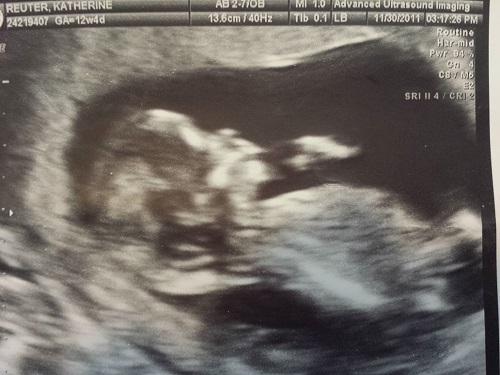

Boy or Girl Skull??? Please guess asap

This picture is from over a year ago and this baby is currently 17 months old. Does the skull look like a girl or a boy? I wanted to see how accurate your guesses are since I am currently pregnant again and you have already made guesses on my skull from this current picture and I am due next month.

As you can see I am totally insane and going crazy as to what I am having next month....haha so just want to see who gets it right!! Thanks everyone! I appreciate you all putting up with my craziness!!